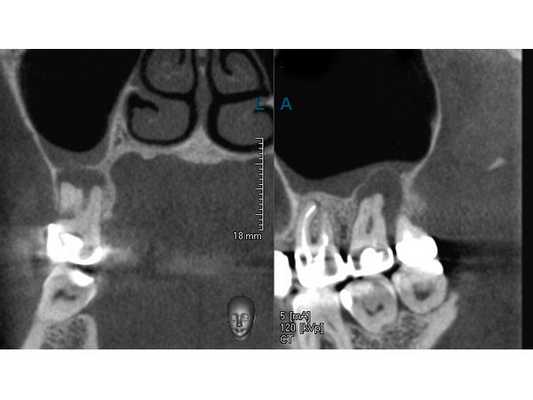

В поликлинике "Наша Клиника-Дент" проведено визиографическое обследование свищевого хода, предварительно в него был введён гуттаперчевый штифт для уточнения локализации воспалительного процесса. Выявлен очаг воспаления в области корней 17 зуба. Также обнаружен участок повышенной плотности, по конфигурации соответствующий фрагменту инструмента в мезиально-щёчном корне 16 зуба.

После протезирования временной коронкой пациентка не предъявляла жалоб. На контрольной томограмме в сентябре 2019 года наблюдается уменьшение очага деструкции, восстановление дна гайморовой пазухи. Рекомендовано обратиться к врачу-ортопеду для протезирования постоянной ортопедической конструкцией. Осмотр в марте 2020 года.